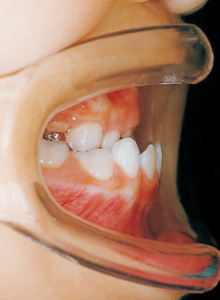

7 1-22-’80 Beginning of first phase

Aware that treatment would be challenging, we proceeded with the first phase of treatment based on the current functional status and anticipated developmental implications (7). During the mixed dentition phase, the body responds readily to treatment, allowing for relatively rapid tooth movement and changes in jaw position (8,9). Subsequently, once freed from mechanical stimulation, growth continues according to inherent predispositions, often appearing to disregard occlusal functional efficiency (10,11). These changes are clearly observable on cephalometric radiographs (12). After confirming the extent and direction of growth, we decided to incorporate surgical intervention into the treatment plan and wait until the age when growth begin to decline.